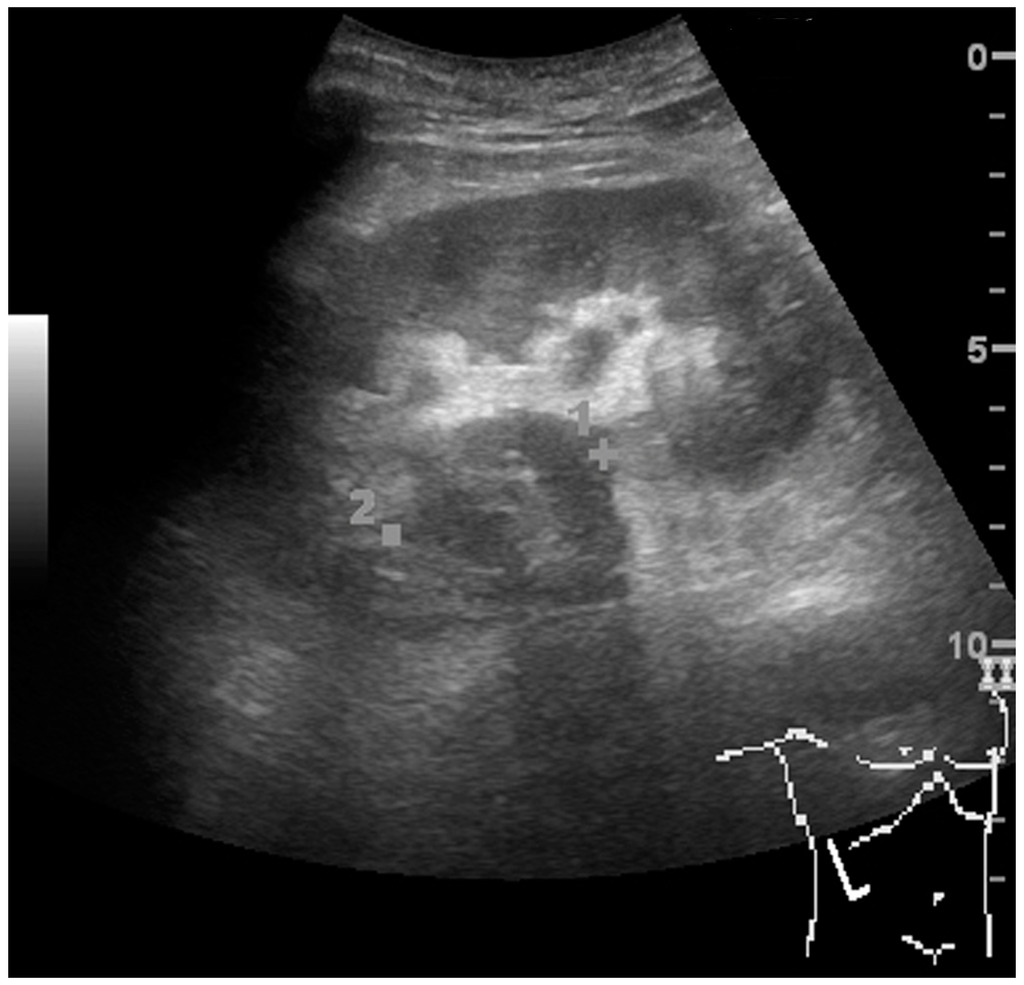

Other malignant tumors in the kidney are transitional cell carcinoma and squamous cell carcinoma, which arise from the urothelium and are found the renal sinus, as well as adenocarcinoma, lymphoma and metastases, which can be found anywhere in the kidney (Figure 10) [2,4].

Figure 10. Solid tumor in the renal sinus seen as a hypoechoic mass, later found to be lymphoma. The ‘1’ and ‘2’ on the US image are reference points used for CT fusion (not shown).